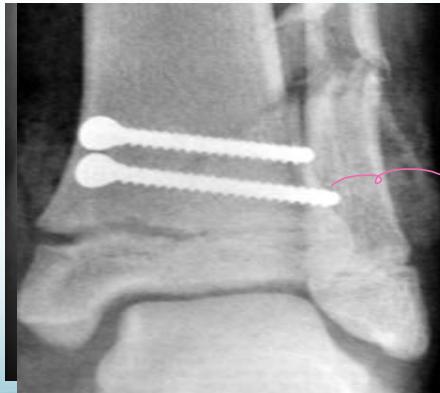

- Unstable: K-wire / screws with cast

Case Example: 12-year-old male, Salter-Harris Type II